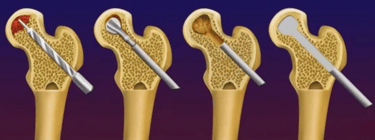

Em relação ao tratamento, não existe uma medicação específica para tal patologia. Casos iniciais, ou seja, em que a esfericidade da cabeça femoral está preservada, o tratamento é feito com uma cirurgia chamada de descompressão ou foragem, na qual remove-se o osso necrótico com uma broca, seguida da colocação de enxerto no local, para estimular a formação de osso normal.

Faz-se o tratamento com a prótese de quadril em casos avançados, ou seja, em que houve colapso/retificação da cabeça femoral ou quando já existe artrose instalada.

Como trata-se a fratura típica de fêmur?

Caso os exames apontem a presença de uma microfratura ou espessamento na cortical lateral do fêmur, é mandatório que seja feita uma cirurgia preventiva, com a colocação de uma haste metálica dentro do fêmur, para evitar a ocorrência de uma fratura completa, uma vez que essas fraturas têm um processo de consolidação mais difícil do que fraturas convencionais, justificando a realização da cirurgia profilática.

Caso ocorra a fratura completa, o paciente apresenta muita dor na coxa e não consegue se levantar. Desse modo, esses pacientes geralmente são levados de ambulância para o hospital, necessitando de internação e cirurgia em caráter de urgência.